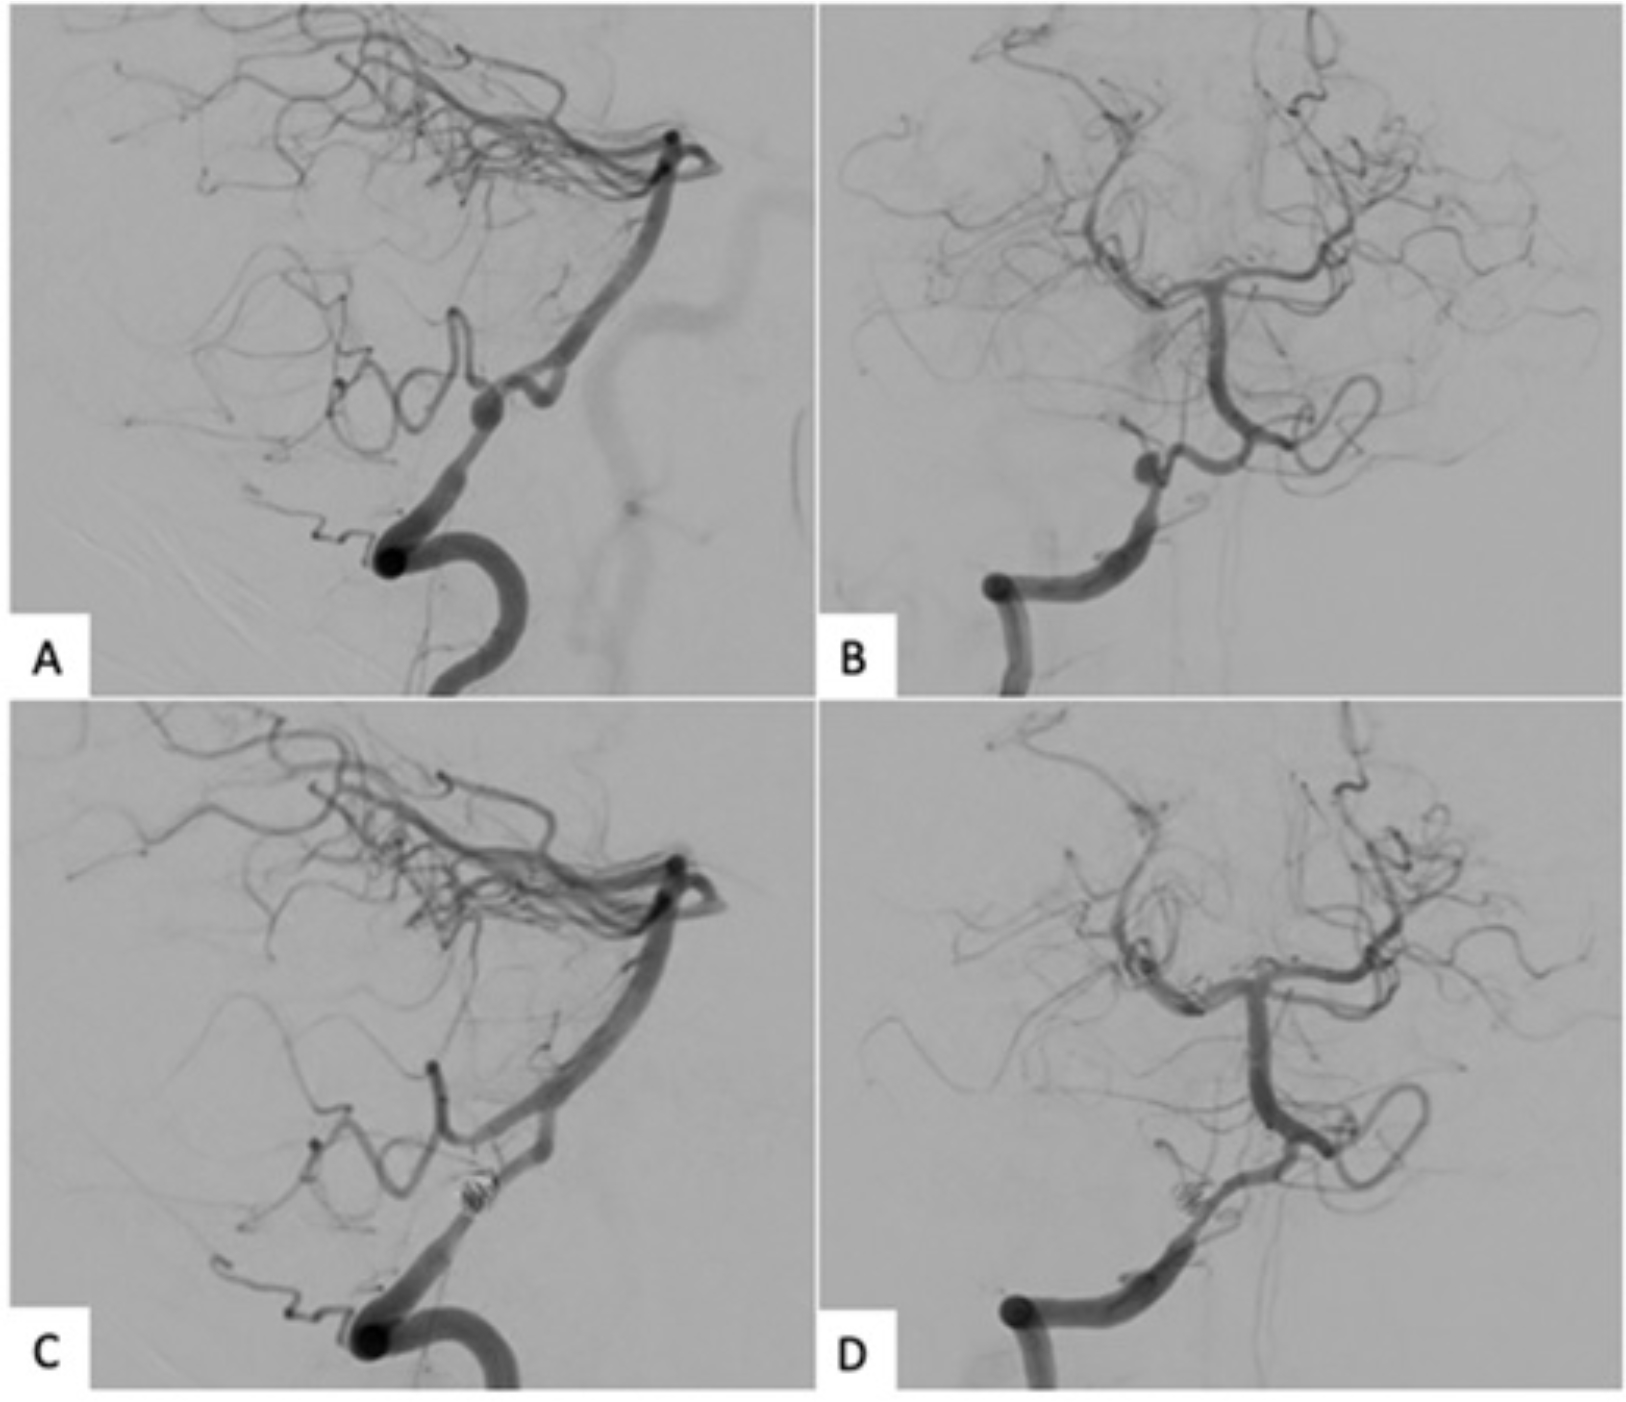

Abstract Image